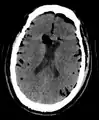

Pneumocephalus and comminuted fracture of the frontal sinus

CT scans of patients with a tension pneumocephalus typically show air that compresses the frontal lobes of the brain, which results in a tented appearance of the brain in the skull known as the Mount Fuji sign.[1][2][3] The name is derived from the resemblance of the brain to Mount Fuji in Japan, a volcano known for its symmetrical cone. In typical cases, there is a symmetrical depression near the midline (such as the crater of a volcano), due to intact bridging veins.[3] Its occurrence seems to be limited to tension pneumocephalus (not occurring in pneumocephalus without tension).[4] The sign was first described by a team of Japanese neurosurgeons.[5]